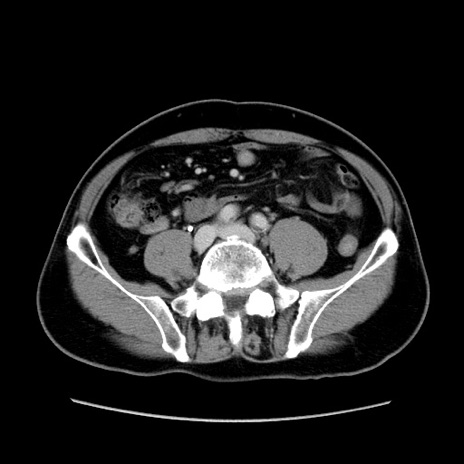

症例34(横断像)

【症例】60歳代 男性

【主訴】右鼠径部膨隆

【現病歴】1年程前より右鼠径部膨隆あり。自己にて還納可能だったため放置していた。3時間前より右鼠径部の脱出を認め、還納困難となり受診。

【既往歴】高血圧

【身体所見】右鼠径部に小児頭大の膨隆あり。弾性硬であり、用手還納は困難。左鼠径部にも膨隆を認める。脱出はなし。

【データ】WBC 15500、CRP 測定なし